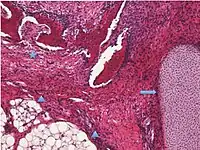

Surface epithelial-stromal tumor | Serous tumor | 25% | 18.5% | Benign serous tumors of the right ovarian cyst are thinwalled unilocular cysts that are lined by ciliated pseudostratified cuboidal or columnar epithelium.[6] | ![]() |